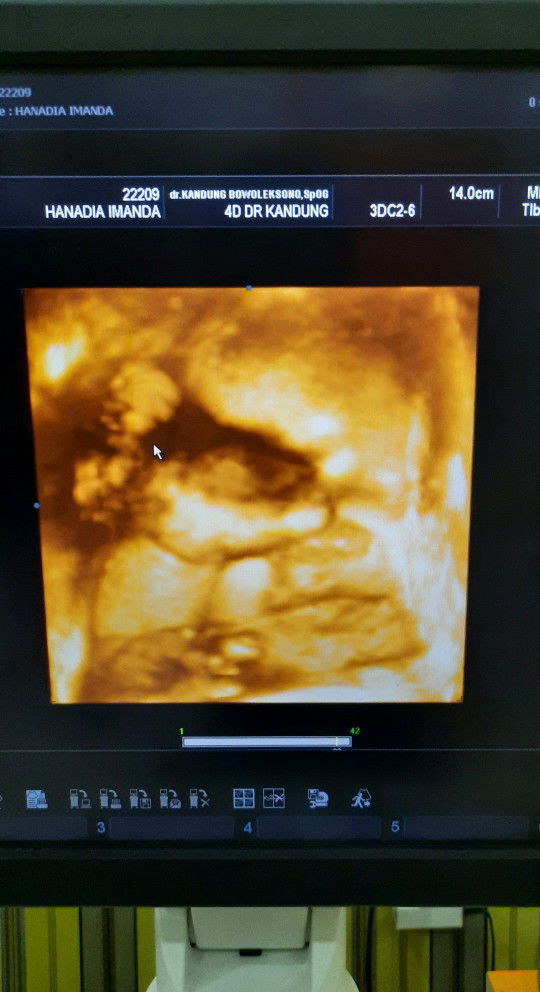

30w4d ?

Akhirnya setelah nunggu 2bulan lamanya posisi baby udah ngga sungsang dan akhirnya juga bisa liat muka baby melalui usg 4D ? mohon doa nya yaa bunda supaya posisi baby tetep mapan sampe hari H dan dilancarkan proses persalinannya.. doa yg sama juga terucap untuk bunda2 yang sedang menunggu baby launching ?